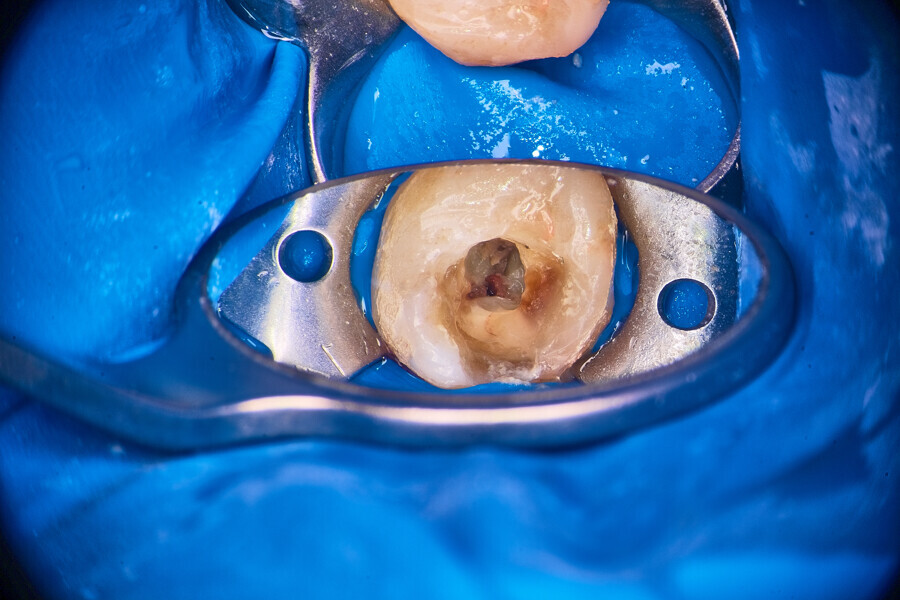

An access cavity had already been created by the referring dentist. During visualisation of the pulp chamber (Fig. 22), remnants of the pulp were identified. In order to properly identify canal orifices, cleaning of the pulp chamber was necessary. This is standard protocol for every endodontic treatment, and it is very important in order not to transport debris from the pulp chamber to canal space. This procedure was done using an Er,Cr:YSGG laser with a wavelength of 2,780 nm (Waterlase, BIOLASE) and RFPT5-10 tip (Fig. 23). After this procedure, which should be done according to the protocol of 1 minute of continuous activation and 1 minute of rest (Fig. 24), the operator can start the instrumentation protocol.

Fig. 21

Fig. 22